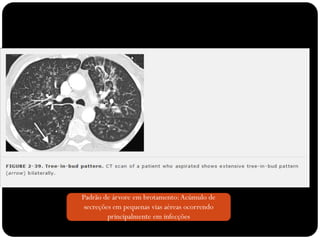

Padrão de árvore em brotamento:Acúmulo de

secreções em pequenas vias aéreas ocorrendo

principalmente em infecções

Sinal de árvore em brotamento

Padrão de árvoreem brotamento:Acúmulo de secreções em pequenas vias aéreas ocorrendo principalmente em infecções